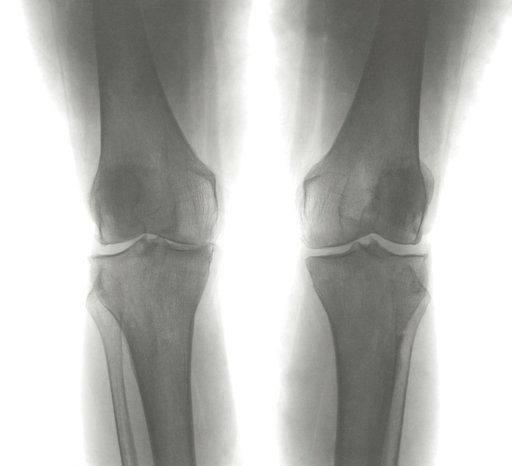

Όλα τα είδη αρθρίτιδας έχουν κοινό χαρακτηριστικό τη φλεγμονή, η οποία εστιάζεται κυρίως στον υμένα της άρθρωσης, και προκαλεί το πρήξιμο, τον πόνο και τον περιορισμό της κινητικότητας.

Οι συνήθεις ενδείξεις για την εφαρμογή της είναι η ρευματοπάθεια, οστεοαρθρίτιδα, φλεγμονώδης αρθροπλαστική γόνατος και η χρόνια συλλογή υγρού στην άρθρωση.